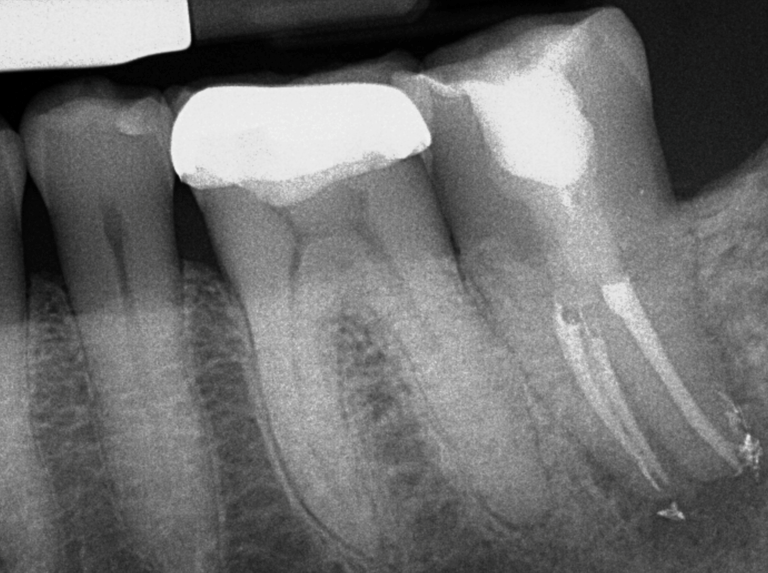

Thorough diagnostic testing and x-ray (radiographic) imaging will be completed to ensure an endodontic problem exists and if it’s the tooth with previous root canal treatment. Additionally, Cone Beam CT 3D imaging will be required to help identify the cause of failure, and to give exact and proper measurements needed for the procedure. Your medically history will also be thoroughly reviewed. The prognosis and description of intentional replantation will then be explained to you.

Treatment Completed by Dr. Battista